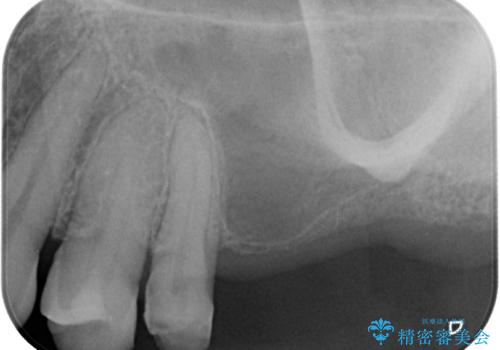

- 口を開けたときに目立ってしまう銀歯をセラミックに替えたいとのことで来院された患者様です。

以前むし歯治療を受けたときは時間がなかったため、近医で銀歯を入れたようですが、周囲の目線が気になるとのことでフルジルコニアクラウンにて補綴することとしました。